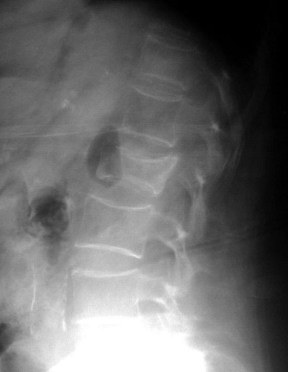

SIGNO DE LA CUERDA COMBADA

Signo de enfermedad de Legg-Calvé-Perthes (osteonecrosis de la cabeza femoral) evolucionada. Consiste en la existencia de una línea curva radiodensa en la base del cuello femoral (flecha) que, probablemente, representa el borde anterior o lateral de una cabeza femoral severamente deformada.